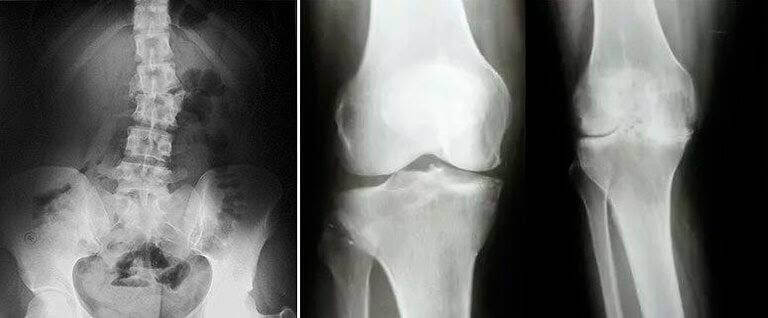

У лікарні аналізи взяли. Лікар молодий, хороший попався, але каже - вибач, на ноги ми тебе поставити не зможемо. Суглоби твої розсипаються вже, запалення знімемо, але нехай твої родичі інвалідний візок готують. Загалом, ходити не зможеш, треба протезуватися.

Та й хребет теж у поганому стані. Каже мені - постарайся пільгу вибити на протезування, та чекай черги своєї, а поки що оформляй інвалідність.

Після цього я прийшов сам до лікарні, то лікарі там ледь зі стільців не попадали. На МРТ мене водили, просвічували всі, дивилися, дивувалися. Потім один сказав, що перші знімки браковані були, тому що артрит не виліковується. А в мене вони його не знайшли! Це як таке? Я лише посміхнувся на це.